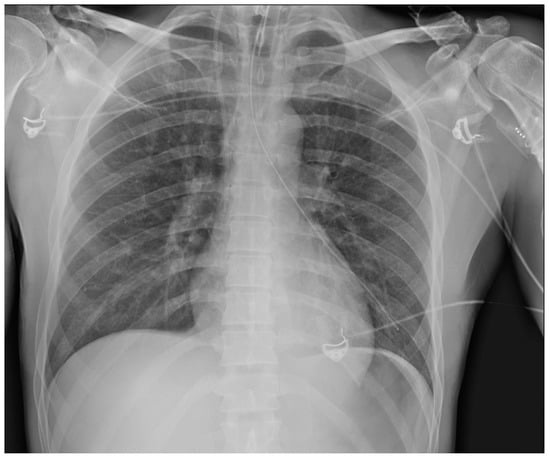

4. Airway Devices

4.1. Endotracheal Tubes